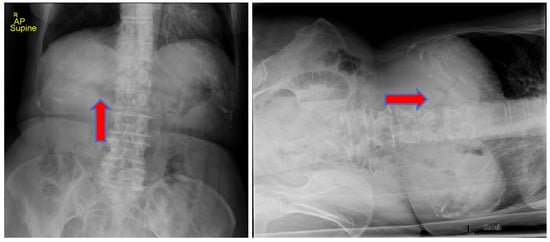

We report the case of an 83-year-old woman who presented to our emergency department (ED) with progressive worsening abdominal pain, nausea, and non-bloody, bilious emesis of one day’s duration that continued overnight in the ED. Her medical history includes coronary artery disease status following angioplasty and stenting, in addition to choledocholithiasis with acute cholangitis requiring endoscopic retrograde cholangiopancreatography (ERCP) with sphincterotomy and percutaneous transhepatic biliary drainage (PTCD) approximately one year prior in her home country, Scotland. Regrettably, the patient’s PTCD tube became dislodged, and she began to develop severe abdominal pain, prompting presentation to our facility. There was no recent history of fever, jaundice, acholic stools, or dark urine. A two-view abdominal radiograph was initially obtained showing a branching density over the liver relating to portal venous gas (Figure 1). Computerized tomography (CT) of her abdomen showed circumferential mid-jejunum bowel wall thickening with a mildly dilated bowel proximally, prominent mesenteric edema, mild intra- and extrahepatic biliary ductal dilatation with pneumobilia, perigastric inflammation, a contracted gallbladder, and probable obstructing mass in the first portion of the duodenum (Figure 2). She developed peritoneal symptoms and was taken urgently for an exploratory laparotomy.

Figure 1. Abdominal radiograph showing branching density over the liver indicating portal venous gas (red arrow). The figure on the left is a supine anteroposterior (AP) chest view and on the right is a left lateral decubitus chest view.